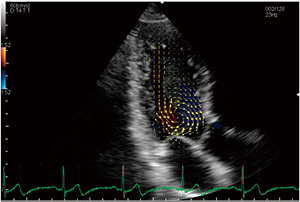

等容収縮期の左室の速度ベクトル表示例を図1に示す。拡張期に流入した血液が左室の基部から中部にかけて大きく旋回し,渦が発生していることがわかる。さらに,図2は図1のベクトルをつないだ流線(streamline)表示である。流れの様子が視認しやすくなり,渦の同定にも有用である。

図1 左室の速度ベクトル表示(等容収縮期) |